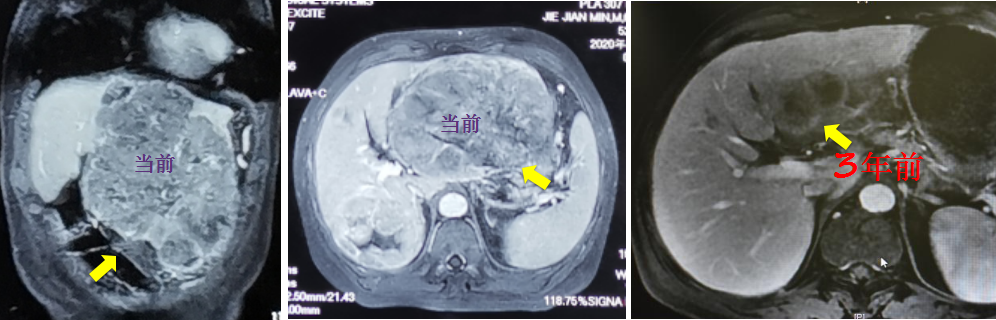

患者曹先生42岁,患肝炎已有数年,平时不注重规范复查,乙肝治疗也时断时续。直到最近一次偶然体检中,曹先生被确诊为肝细胞癌,影像显示曹先生的肿瘤直径已达15cm,同时伴有肝静脉癌栓,属于无法手术切除的晚期肝癌。一时间,曹先生认为自己的日子“所剩无几”,情绪极度焦虑。

如曹先生这般,因为肝脏肿瘤发现较晚,就自暴自弃,也是错误想法。随着医疗技术的发展,近两年上市的靶向治疗和免疫治疗极大提高了肝癌的治疗效果,通过多学科联合治疗(MDT)能够为众多中晚期肝癌患者制定大幅延长生存期的科学治疗方案。针对伴有门静脉或肝静脉癌栓等不可切除的中晚期肝癌,目前正在兴起转化治疗,其目的是通过一系列针对性辅助治疗,让大肿瘤缩小或者坏死,让癌栓退缩,从而把不可切除的肝癌变为可切除,其有效率可以达到30%左右。

针对曹先生,清华长庚医院董家鸿院士团队为其制定了“放疗+靶向治疗+免疫治疗”的前期转化治疗方案。在放疗科黎功主任的主持下,经过精准放疗,患者的肿瘤明显缩小,肝静脉癌栓也消失了。然后,肝胆外科杨世忠接手了后续的外科治疗,为患者实施了持久美兰染色引导的精准右半肝切除。目前,术后1年,患者生活状态正常。